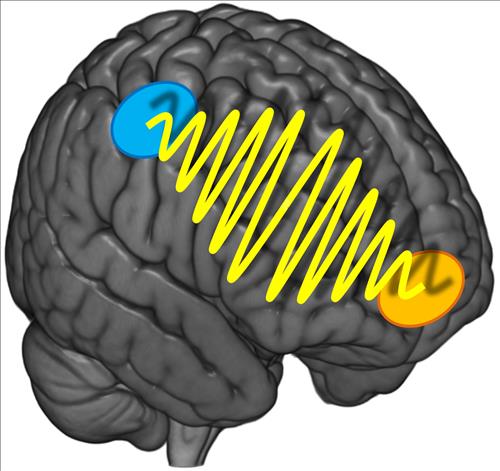

'자장면? 짬뽕?' 결정 어려운 건 뇌 신호 문제

스위스 연구진 "결정 잘 못하는 사람은 뇌 부위간 신호흐름 부족" (대전) 이주영 기자 = 사람들이 식당에서 음식을 주문할 때 선뜻 결정을 내리지 못하고 고민하는 이유는 무엇일까? 또 이런 결정력에서 사람들...

IT/과학 | 08-21 17:31